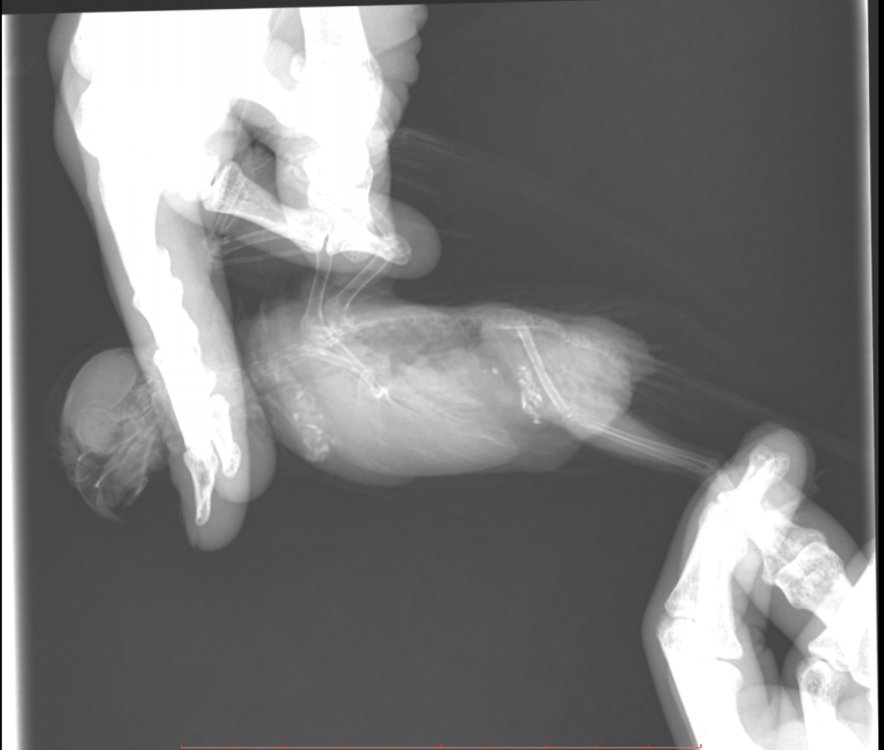

Во вторник отвозила птицу на рентген. Врач сказала, что очень сильно увеличена печень и другие органы. Также сдавлены воздухоносные мешки (из-за увеличенных внутренних органов). Отсюда - одышка. Также врач нашла перелом (старый?) ключицы. Попугая было очень сложно удерживать, поэтому снимки получились, возможно, недостаточно информативными - но какие уж получились((

@Zosia здравствуйте! Посмотрите, пожалуйста, снимки - видите ли вы на них отклонения, опухоли? Есть ли какие-то патологии? И одобряете ли вы назначенное лечение в нашей ситуации? Спасибо!

2.jpg

4.jpg

Печень видится мне увеличенной, но нужно чтобы @Zosia достоверно прочла снимки.

ответ: я увидела на снимках запущенную пневмонию, увеличенные семенники (и возможно опухоль на них), увидела в помете много палочек. Отсюда - назначение.

6.Тень семенников действительноу величена. Но снимок вами показан дурного качества. И бОльшего я сказать не могу.